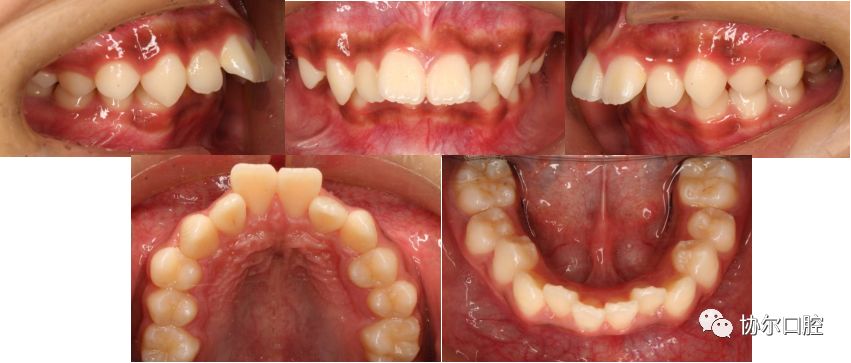

关键词:下颌后缩;前突;生长发育

矫治方法:拔牙矫治,微种植体支抗技术

矫治时间:24个月

治疗前口内相

治疗后口内相